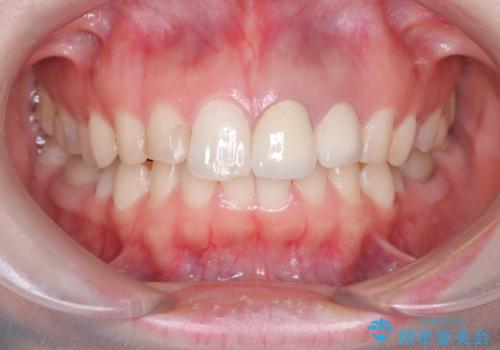

「数日前から前歯に痛みがある」「左上1、2番の色が気になる」

左上1番および2番は失活歯であり、両歯ともに失活に伴う変色を認めました。左上2番に関しては根尖部に透過像を認め、根尖性歯周炎と診断しました。これが前歯部の痛みの原因と考えられました。

左上2番に対して精密根管治療を実施し、感染源の除去を行いました。その後、左上1、2番ともにオールセラミッククラウンによる補綴を行い、審美的な修復を行いました。

痛みは消失し、患者様の審美的な満足度も高く、良好な治療結果が得られました。